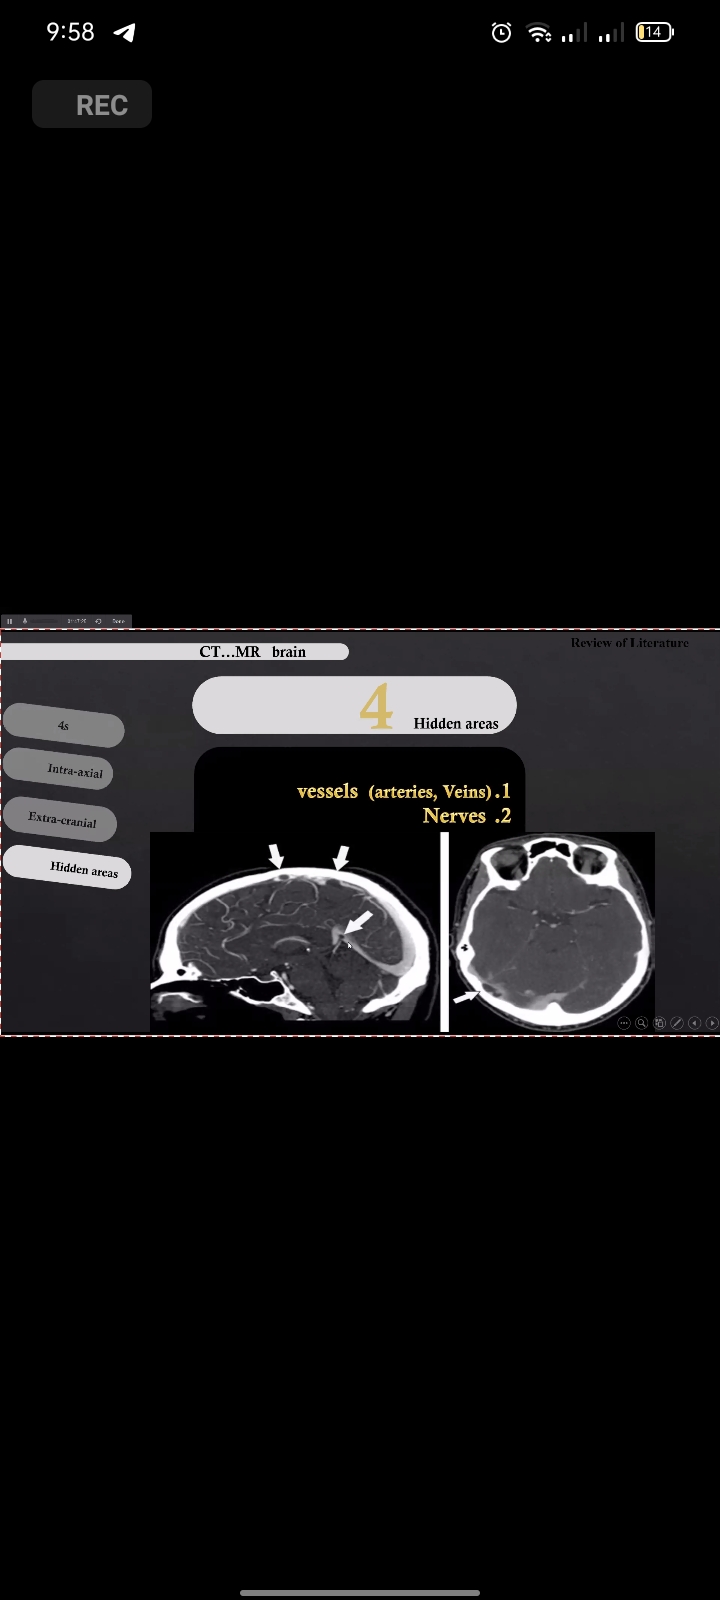

Medicaspace appreciates the effort made to make the radiology reporting course a success.

We are so proud that we are the responsible for organizing this successful course, which was attended by more than 500 individuals. With sincere thanks to the Egyptian society of radiology and all the doctors

Dr. Hesham Elsheikh

Dr. Talal Amer